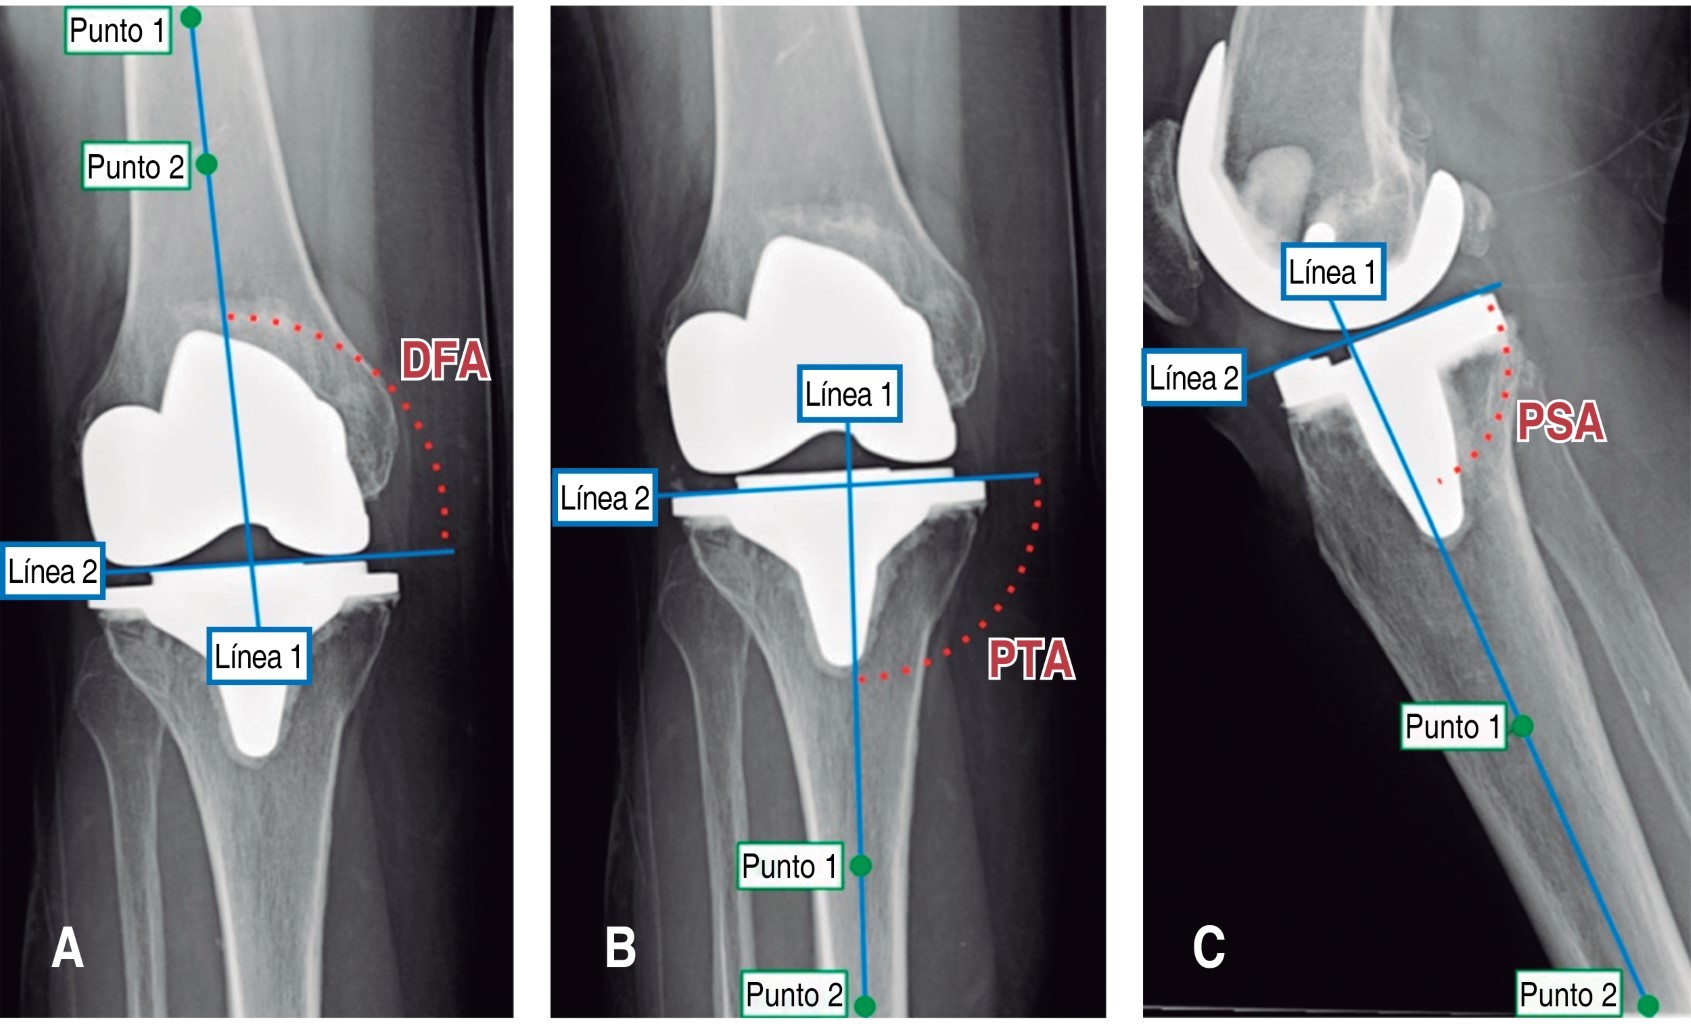

Varios autores han encontrado que cuando el ángulo medial distal femoral (DFA) (1°-7° de valgo), ángulo medial tibial proximal (PTA) (90° ± 3°) y el slope tibial posterior (PSA) (0°-7°) se encuentran fuera del rango (Figura 1), aumenta el riesgo de fallo del implante a largo plazo, de hecho, mientras más se alejan los valores de rango es mayor el riesgo de fatiga del mismo.1,6,11,13,17

Se midieron el DFA, PTA y el PSA de las radiografías AP y lateral, respectivamente, utilizando una herramienta para medición digital. Una vez obtenidas las mediciones, se dividió a los individuos en cinco subgrupos dependiendo el valor de cada uno de los ángulos.Un grupo control con sus tres mediciones dentro de los rangos normales, un grupo de casos con un valor atípico en DFA, uno con valor atípico en PTA, otro con valor atípico en PSA y finalmente un grupo de casos con dos o más valores fuera de rango.

Figura 1